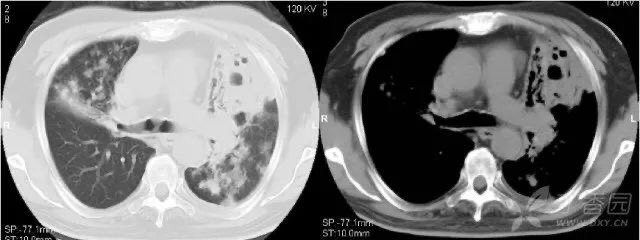

5.2 肺气囊

病理学为肺内薄壁的充气气腔。常为急性化脓性肺炎(金黄色葡萄球菌肺炎等)、外伤、吸入碳氢化合物液体所致。发病机制是实质坏死和活瓣性气道阻塞的综合作用。

金葡菌肺气囊形成是由于支气管周围脓肿,而使终未细支气管和肺泡发生坏死,空气进入肺间质内,加上小支气管内的炎性渗出物,引起活瓣性阻塞,形成肺气囊,表现为大小不等的类圆形薄壁空腔,其大小、数目、位置可随时间不同而表现不同,变化快。

5.3 肺大疱

肺大疱的壁甚薄,由肺泡的扁平上皮细胞组成,也可能仅为纤维性膜。肺大疱是由于各种原因造成管腔部分阻塞,产生活门作用,空气能进入肺泡而不易排出,肺泡内压力增高,肺泡间隔逐渐因泡内压力增加而破裂,乃形成巨大的含气囊腔。

多位于胸膜下,大小在 15 mm 以上;有学者认为肺实质内部直径大于 25 mm 的含气囊腔可诊断肺大疱,常见于肺气肿患者。

右肺实质内可见巨大含气囊腔,壁菲薄/无壁,为少见的肺实质内巨大肺大疱;左肺胸膜下可见多个肺大疱。